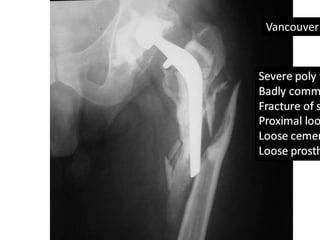

• Vancouver B3 type peri-prosthetic fracture

Vancouver B3

• Severe bone loss from acetabular walls

• Iliac bone grafts were packed

• Revision of acetabular cup was done and was

fixed with three screws